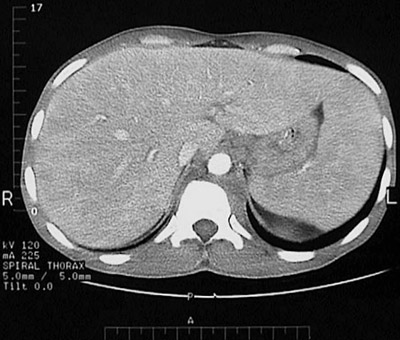

![]() | Immunocompromised persons can develop disseminated fungal infections that can affect many organs, particularly organs of the mononuclear phagocyte system. Thus, there is both hepatomegaly as well as splenomegaly seen here in a patient with disseminated histoplasmosis. The spleen and liver abut one another. The infectious foci containing the Histoplasma capsulatum organisms in macrophages are so small as to be invisible, but so numerous as to enlarge the affected organs. |